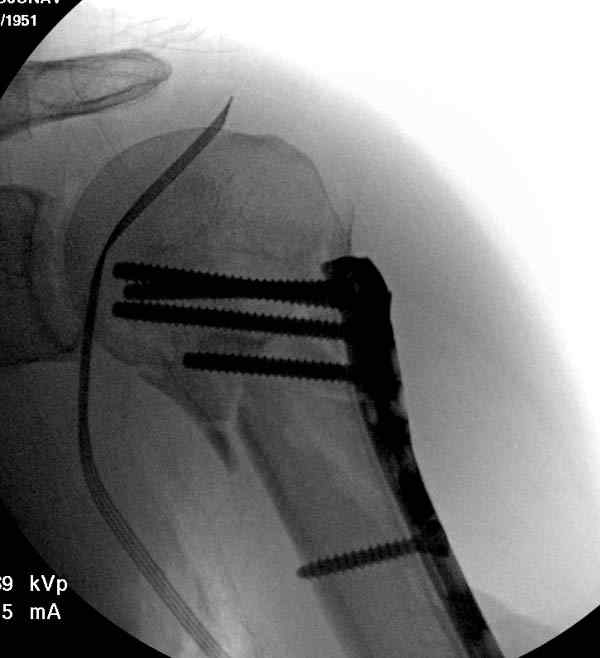

После устранения смещения пластина установлена выше (5,6,7) и финальные снимки (8,9,10)

Подбор импланта тоже имеет значение, например многие импланты направлены для фиксации перелома без учета ротаторной манжетки. Предпочтительными являются низко сидящие полиаксиальные пластины, где верхние шурупы можно проводить под углом в 120 градусов. (11)

Пластина от Synthes или ее копии (надеюсь простят критику друзья из Деоста) считаются трудным из-за обширности доступа, особенно при установке верхне-заднего шурупа, где доступ надо расширять в верхнем отделе до ротаторной манжетки. Верхне сидящие импланты предназначены для проведения опоры (buttress) за бугристость плеча, но тогда приходится сталкиваться с подакромиальным импинжментом.